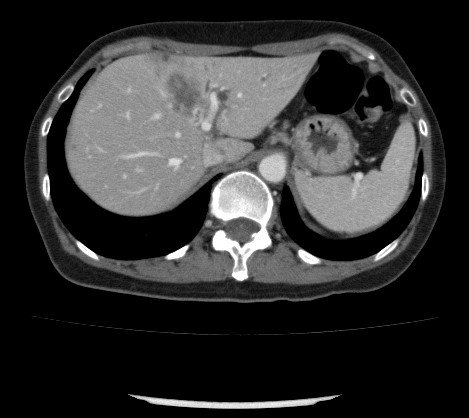

• NET-in qaraciyər metastazlarının xarakterik xüsusiyyəti hipervaskulyar olmasıdır ki, bu da Doppler müayinəsində intensiv axın şəklində, kontrastlı müayinələrdə isə arterial fazada kontrastlaşma və venoz fazada yuyulma əlaməti ilə təyin edilir.

Diaqnostik əlamətləri:

• Hipervaskulyar törəmələr